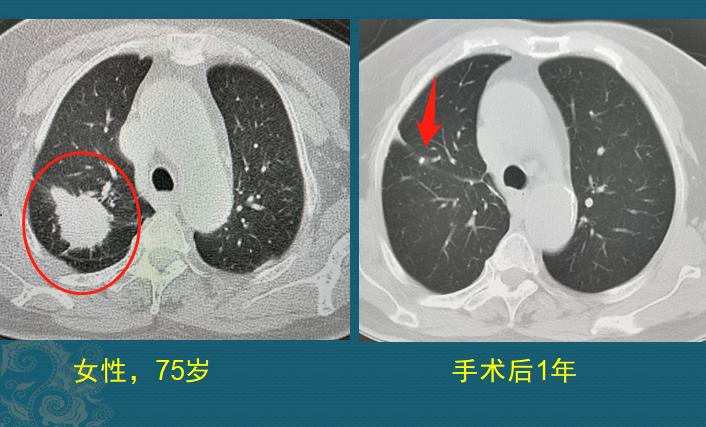

这种的有运气成分,差异比较大!像下图这位老人,75岁,右侧胸痛20天,CT发现4.0cm肺癌(不规则实性肿块,边缘有毛刺和棘突征、胸膜牵拉),没有转移扩散,今年复查恢复很好:

2.中年时候重视体检,戒烟

生长快的肺癌窗口期短,需要运气加持,但生长慢的肺癌可以通过体检筛查出来,科学监控,防止发展为晚期。

下图这位老人就比较幸运,71岁男性,因为心绞痛住院,完善胸部检查时发现右肺高危肺结节,长径1.0cm,形态不规则,幸运的是发展比较慢,3年后增大到1.8cm:

去年做了胸腔镜手术切除右肺上叶,病理是浸润性肺腺癌,今年复查恢复不错!

其实他的手术更早几年做,安全系数更高!肺癌的生长速度不一致,有些人比较幸运,拖几年也没事,有些却可以在几个月内发生转移扩散,不能一概而论,但重视定期体检和早期治疗是最安全的。